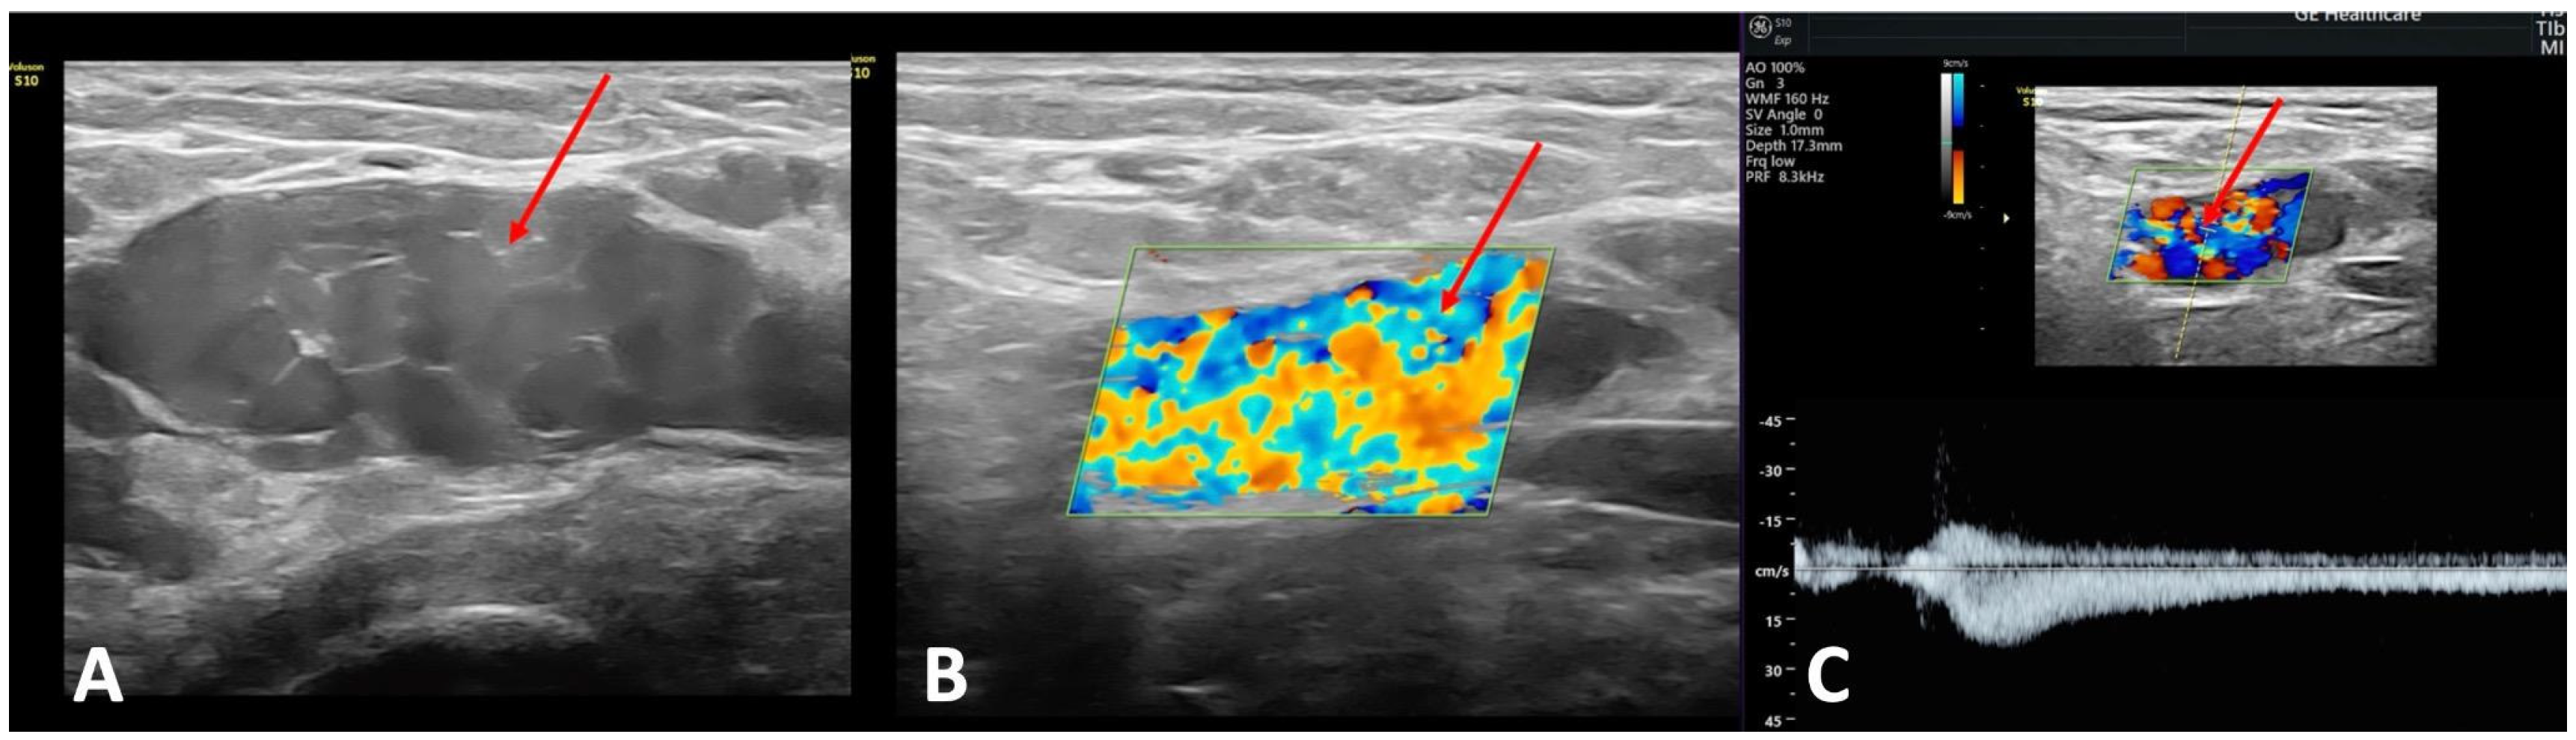

2.2.1. Transvaginal Ultrasonography